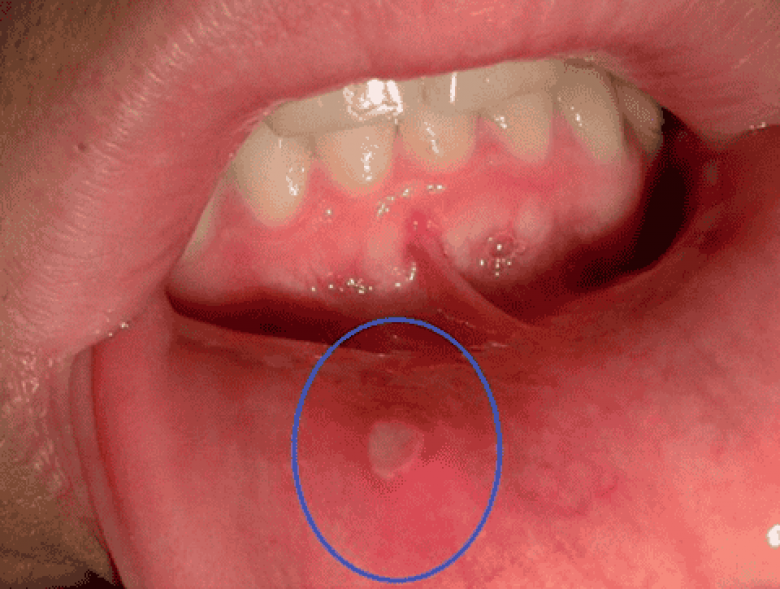

4 Եղունգները կրծելով դուք կարող եք վնասել լնդերը և լեզվի լորձաթաղանթը և անմիջապես վարակ անցկացնեք վերքի մեջ: Եղունգների տակ գտնվող ստաֆիլակոկները ջանասիրաբար կաշխատեն բերանում ստոմատիտ առաջացնելու վրա: